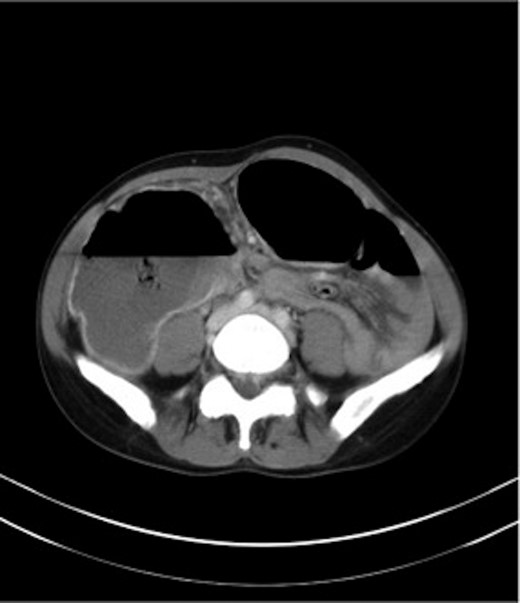

Haemoglobin was 12.6 g/dl and a WCC of 8.3 × 109/l. Other remarkable laboratory tests included a CRP of 19 mg/l. Urinalysis was normal. The AXR revealed a grossly distended large bowel. A CT scan of the abdomen revealed that the rectum, sigmoid and descending colon were collapsed with an apparent calibre change within the transverse colon with no mass lesion (Fig. 3).

CT of the abdomen (Case 2) showing a calibre change within the transverse colon with no mass lesion.